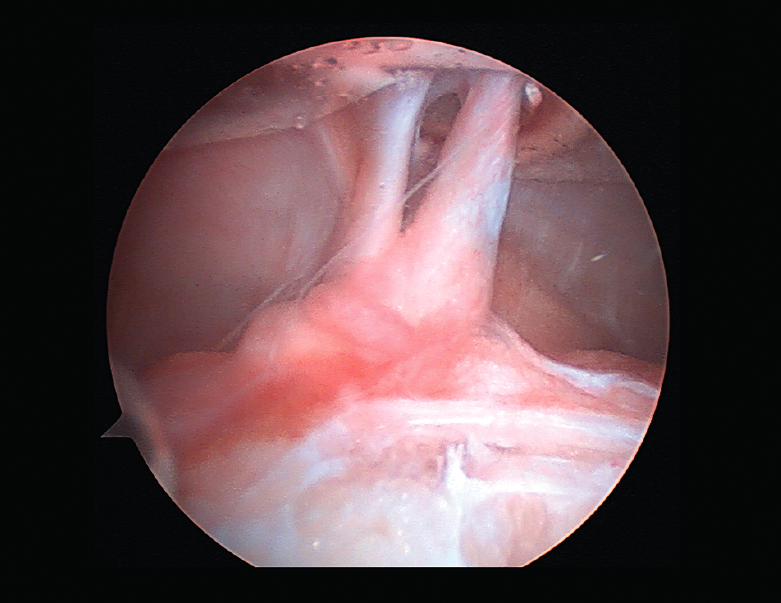

Rigidez

Una de las complicaciones más temidas, producida por un aumento del tejido fibroso, ya sea por la propia lesión (primaria) o secundaria a diferentes motivos (error técnico en la cirugía, síndrome del cíclope, inmovilización prolongada o la participación insuficiente en un programa de rehabilitación, infección, síndrome del dolor regional complejo, hematomas o sinovitis) (Figuras 7 y 8). Esta puede variar desde una ligera limitación del rango de movilidad hasta una severa artrofibrosis(21).

Figura 7. Adherencias intraarticulares.

Las principales causas secundarias a errores técnicos son la malposición de la plastia y el tensado excesivo. La radiografía permite ver la localización de los túneles e implantes, así como la RM visualiza las partes blandas implicadas, pudiendo identificar posibles pinzamientos de la plastia –escotadura intercondílea, síndrome del cíclope (Figura 9), síndrome de la contractura infrapatelar(22)(Figura 10)–.